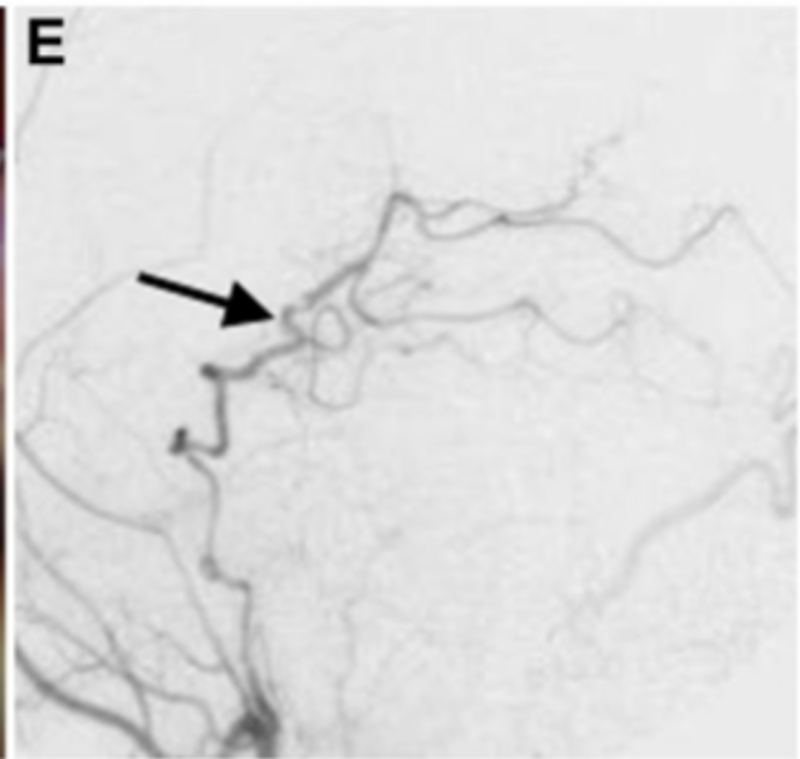

进行STA-PTA旁路手术后,Kawashima教授将远端夹子放置在夹层动脉瘤上,同时保留穿支。术后1周血管造影显示,通过旁路到达左侧PCA区域的血流良好,并且动脉瘤完全被排除(图3E)。两周后,患者出院回家,没有出现神经功能缺损。在1年随访中,患者改良Rankin评分为0,搭桥术仍然合适。

▼E:术后1周的颈外动脉血管造影显示整个左PCA的旁路血液供应良好(箭头)